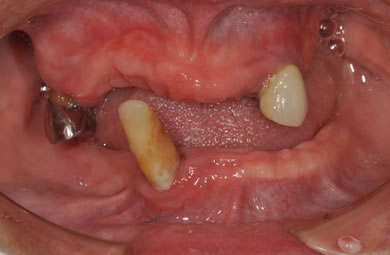

インプラントの症例写真 IMPLANT

骨再生スピードインプラント治療+AGC連結セラミック治療

| 性別/年齢 | 女性 / 57歳 | ||||||||||||||||||||||||||||||||

| 主訴 | 全体的に歯が無いので相談したい。 | ||||||||||||||||||||||||||||||||

| 治療内容 | インプラント12本(サイナスリフト+GBR+抜歯即日スピードインプラント+遊離歯肉移植)、AGCハイブリッドセラミック連結ブリッジ2装置(上顎・下顎)、テンポラリーインプラント2本 | ||||||||||||||||||||||||||||||||